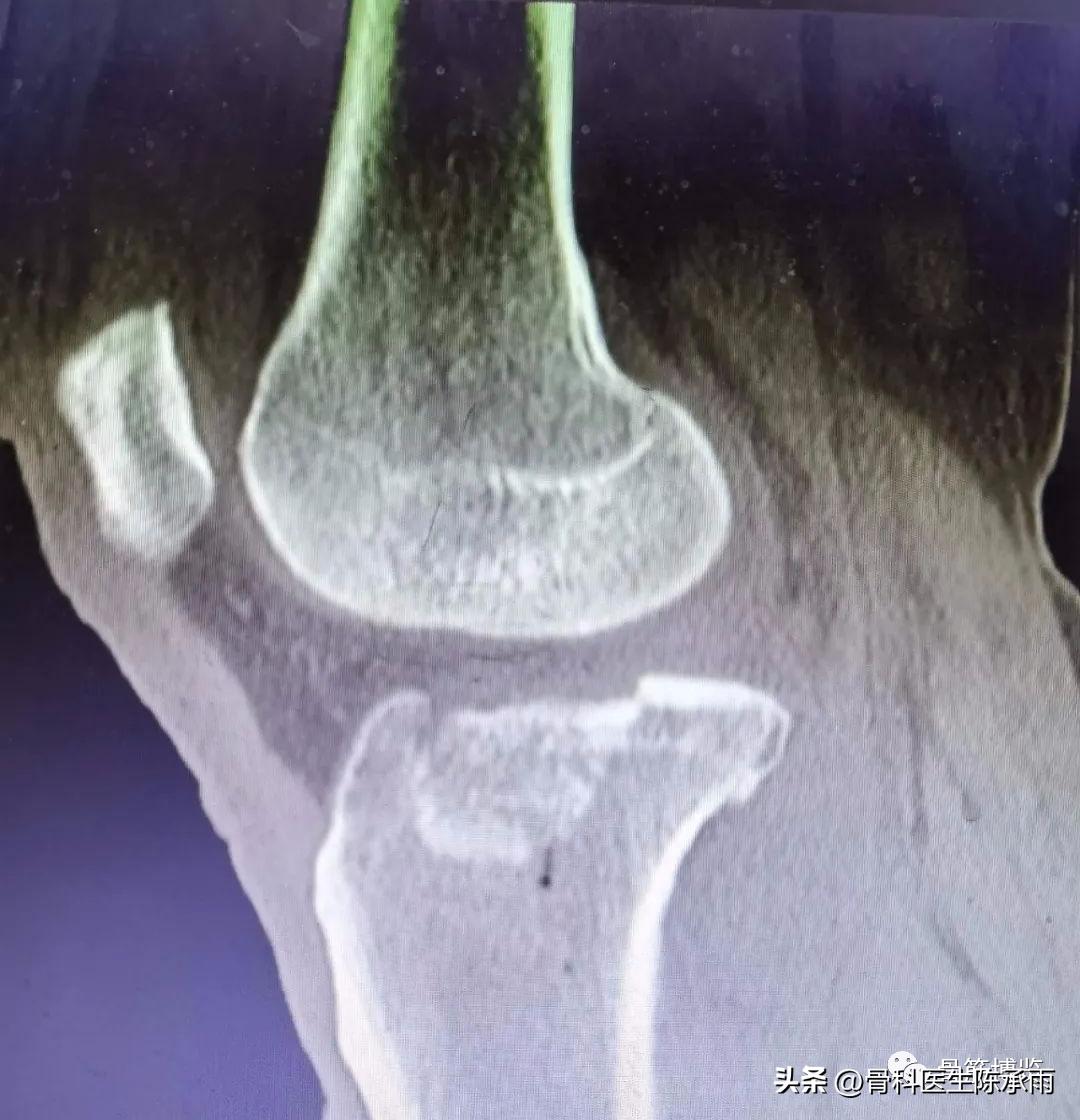

1例

2例

3例

4例

5例

6例

7例